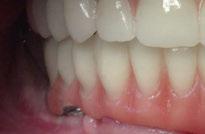

Ejecución técnica quirúrgica mediante férula guiada Bajo anestesia infiltrativa realizamos extracciones atraumáticas de todas las piezas a excepción de los dientes que actúan como anclaje o pilares para la fijación de la férula quirúrgica (Figuras 20 y 21). Seguidamente insertamos la férula comprobando una buena adaptabilidad y estabilidad

(Figuras 22 y 23). Se realiza fresado transgingival mínimamente invasivo y guiado hasta la inserción de los implantes, siguiendo el protocolo preestablecido e indicado (Figuras 24 a 26).

Durante la colocación de los implantes comprobamos una inserción con torque superior a 35 N/cm2

Retiramos la férula y comprobamos una correcta estabilidad primaria mediante mediación de valores

ISQ favorables en la mayoría de los implantes. Seguidamente se extraen los dientes remanentes que han actuado de medio retentivo para la férula quirúrgica.

Dentro de la fase quirúrgica propiamente dicha, una vez terminada la inserción de los implantes y

comprobada su estabilidad primaria, colocamos pilares transepiteliales

Multiplus para registrar una impresión digital mediante escaneado sobre ellos (Figuras 27 a 29)